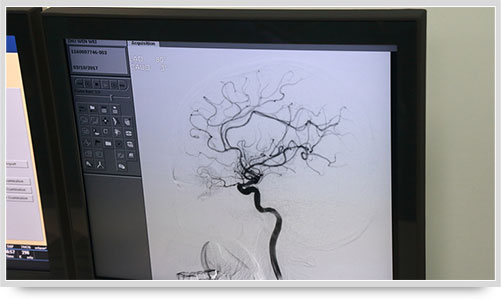

弓上造影、超選到頸內(nèi)動脈、椎動脈......在數(shù)字減影技術(shù)下,注入顯影劑后,導(dǎo)管經(jīng)患者右側(cè)股動脈在體內(nèi)推進(jìn),由于股動脈離腦血管距離較遠(yuǎn),中間“路程復(fù)雜”,對施術(shù)醫(yī)生的要求非常之高。

同時,手術(shù)臺前的液晶顯示儀屏幕上清晰地現(xiàn)顯出導(dǎo)管的路徑,在李主任的操作下準(zhǔn)確到達(dá)指定檢查部位,各條血管的“廬山真面目”清晰可見。